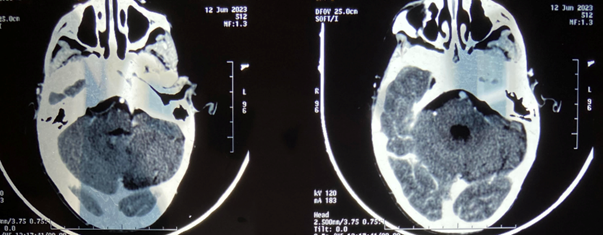

The postoperative period was uneventful, and the patient's symptoms markedly improved within one week. Histopathologic examination confirmed the diagnosis of a hydatid cyst. Albendazole was initiated at a dosage of 10mg/kg/day and continued for three months. The patient was discharged on the fifth postoperative day. In the most recent examination conducted 1 year post-surgery, the patient remains stable. Brain CT scan showed no reccurence (Figure 3).